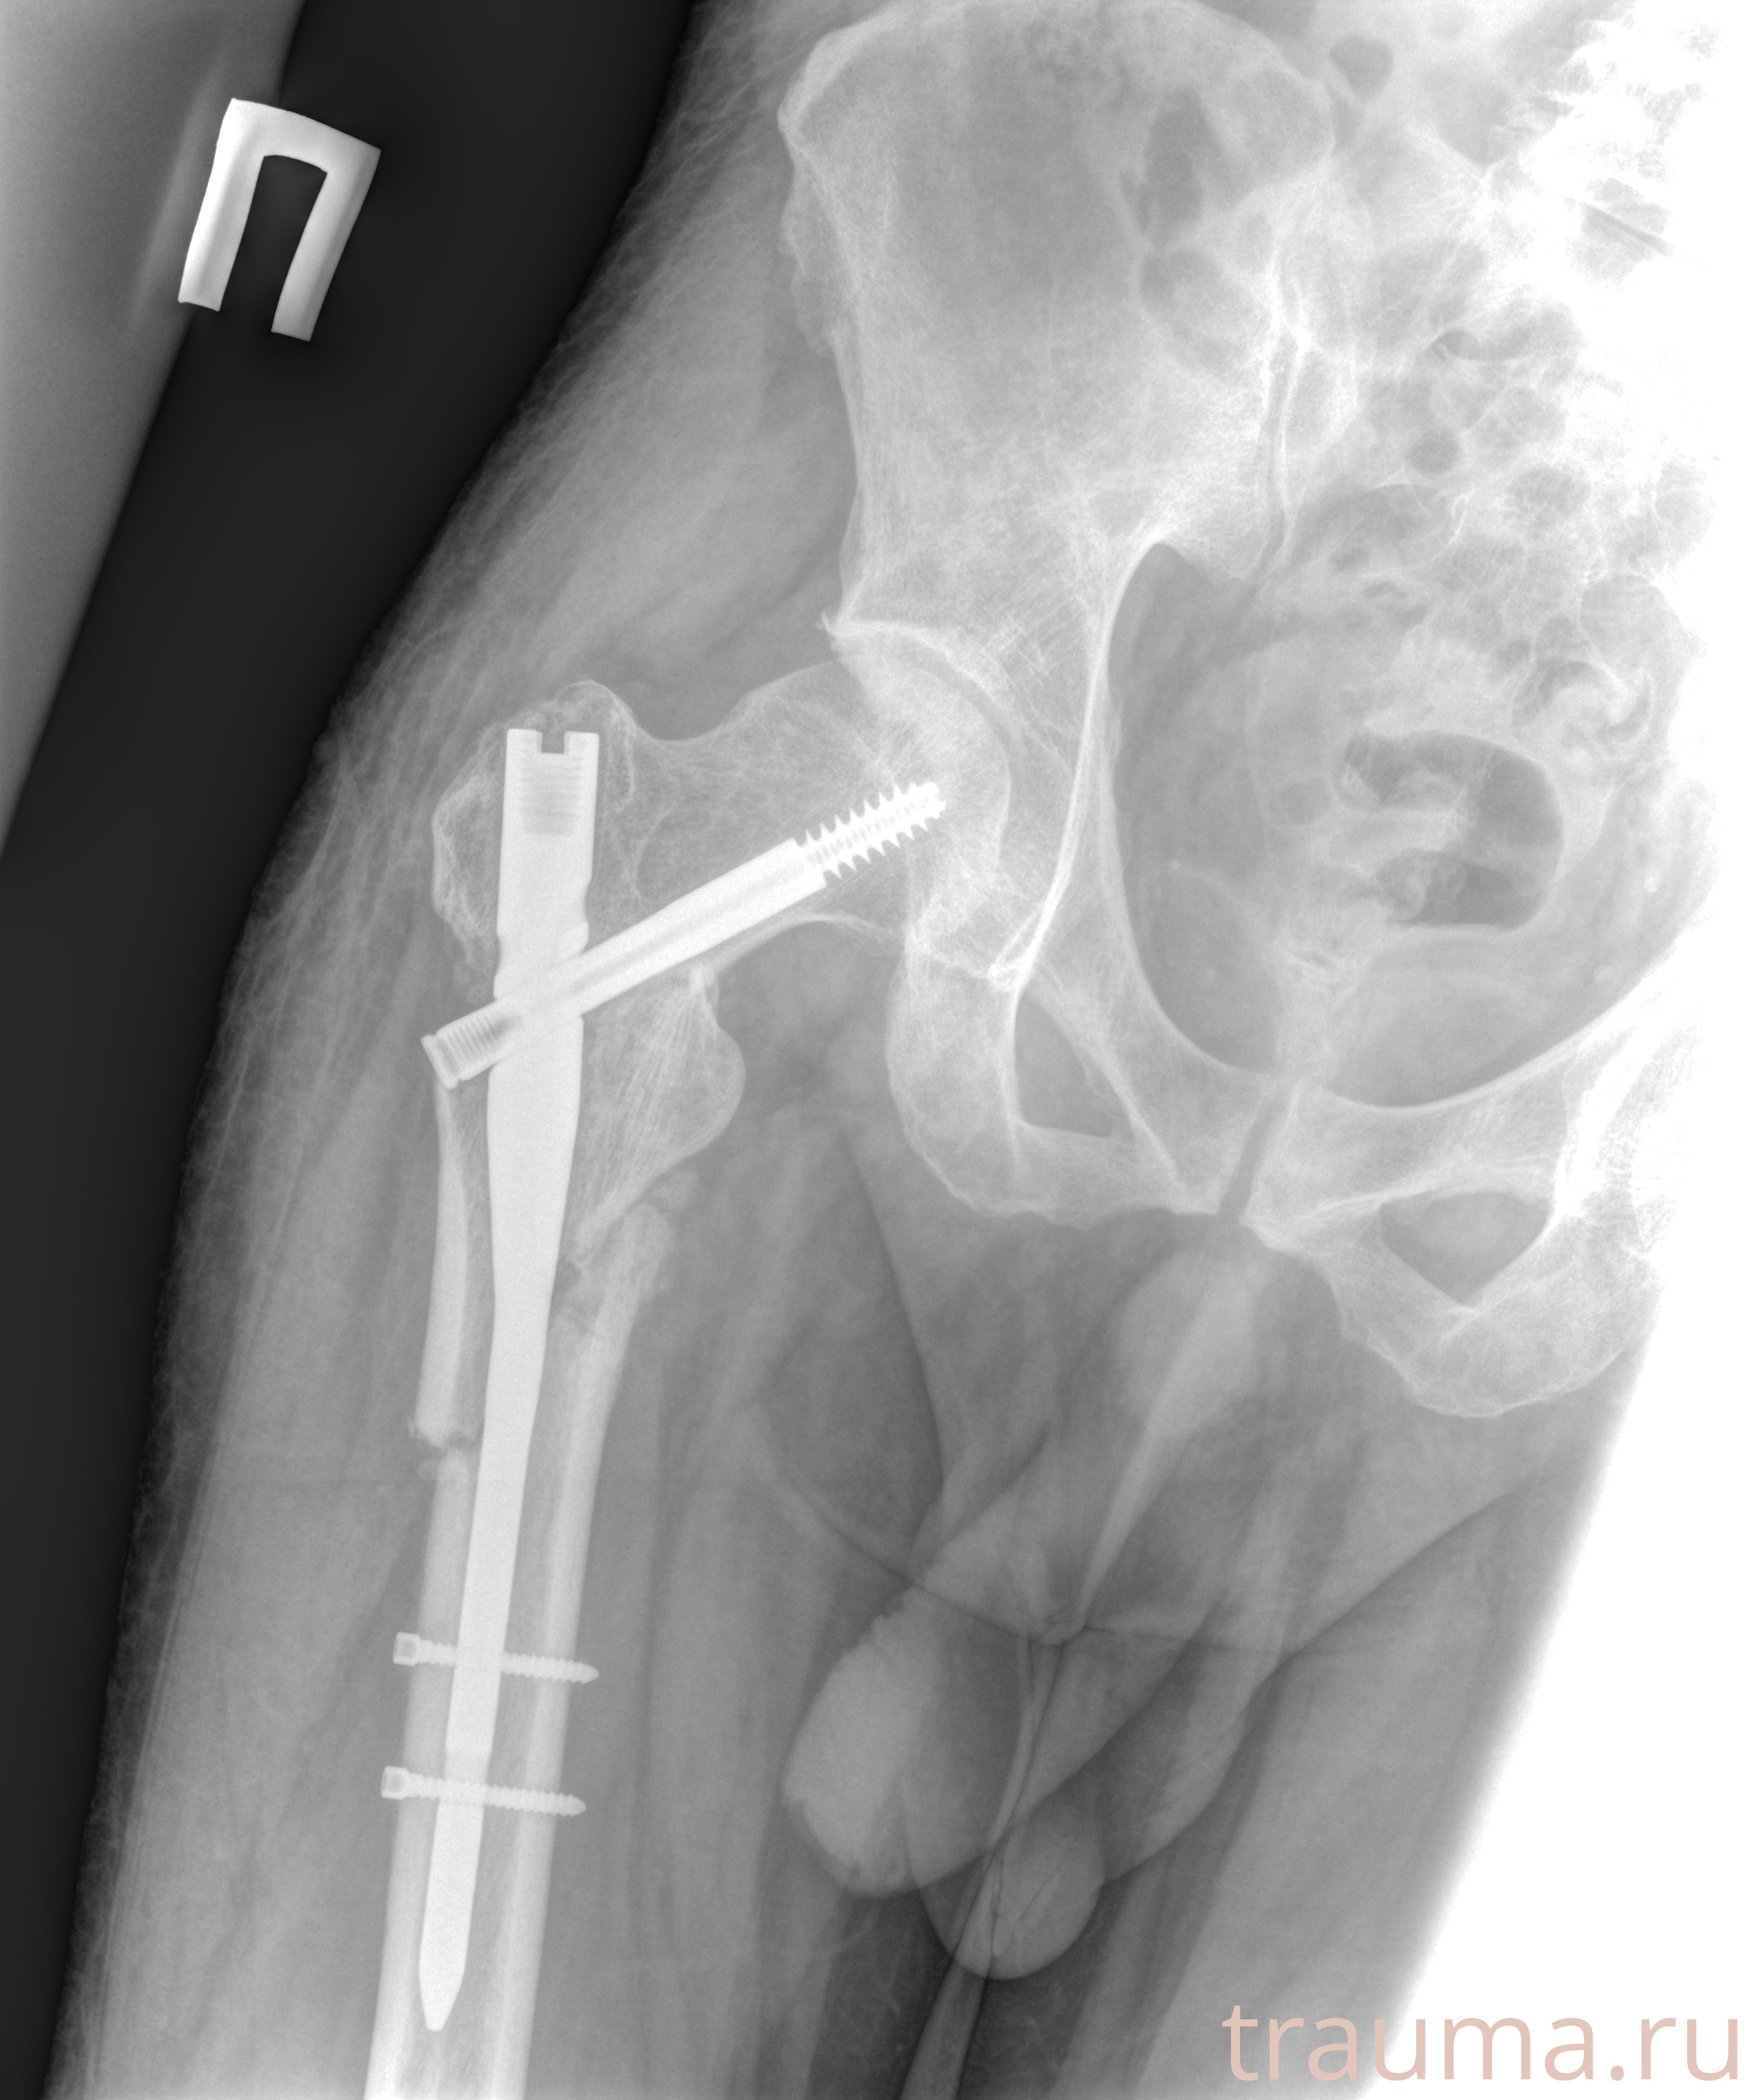

Рентген на дому: по вашему адресу приезжает врач-рентгенолог, травматолог-ортопед с мобильным рентгеновским аппаратом, проводит диагностику травмы или заболевания, делает необходимые рентгенограммы, дает рекомендации по дальнейшему лечению. Получить качественные снимки в домашних условиях возможно благодаря уникальной методике, разработанной МосРентген Центром для института  Склифосовского